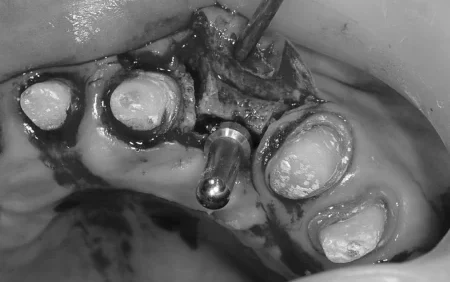

インプラント治療をするにあたり、まず骨幅を広げるために、歯茎を開き歯を支えている骨を慎重に縦に半分に分割し、その隙間にインプラントと骨を増やす材料を一緒に詰め歯茎を縫合する治療「スプリットクレスト」を行いました。

スプリットクレストして骨の幅を広げ、インプラントが入るようにしています。

傷の治りも順調で、骨の盛り足しもうまくいっています。